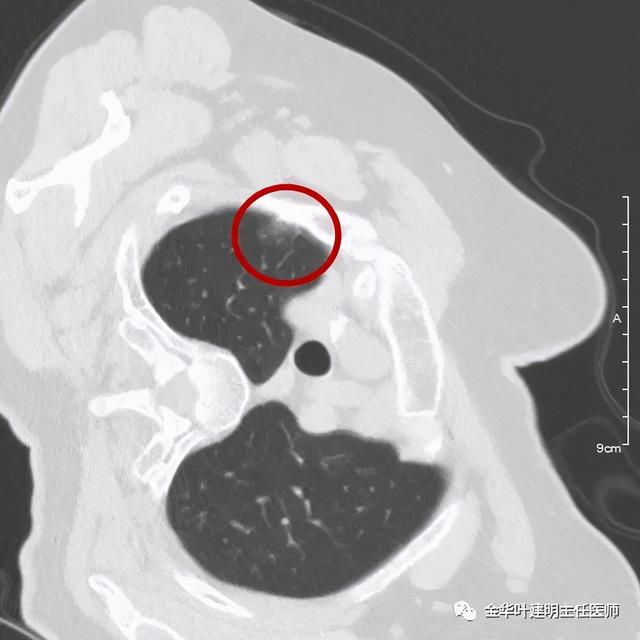

可见右肺上叶混合磨玻璃结节 , 有明显分叶征 , 瘤肺边界虽然欠清楚 , 但轮廓比较清晰 。 看着也许会考虑炎性 , 但总觉得其比较僵硬 , 看去不舒服 。 这种病灶一是如果持续存在就极可能是肺癌 , 二是靶扫描显示更清晰的细节 , 如果瘤肺边界还是清楚的 , 也基本是肺癌 。 我们回顾发现其于2019年3月在我们医院做过CT平扫 , 当时报告如下:

这样看来 , 此结节基本已经确定是早期肺癌了 。 那么我们再来看其靶扫描情况:

靶扫描更清楚显示瘤肺边界较清、分叶及密度不均杂乱 , 并有少许胸膜牵拉凹陷 , 当然考虑是肺癌 , 而且应该是浸润性腺癌了 。 其长径达2.5厘米!靶扫描还发现了平扫没被注意到的另一个病灶: